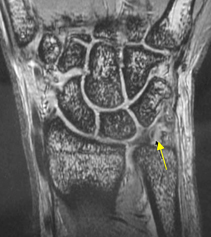

TFCCのMRI画像診断

TFCCのMRI画像診断:矢印部で断裂し、白くなっている(引用文献2より)